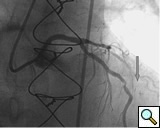

PCI of the vein and arterial grafts have unique challenges. For any PCI, guide support is very important for successful balloon and stent delivery. In a tortuous vein graft with a steep angle, advancement of a stent can be very difficult and challenging. Therefore, it is important to choose the best available catheter before starting PCI. Similar to the right coronary angiography, a JR4 guide catheter is most commonly used in this setting. However, Amplatz guide catheters for left vein grafts and multipurpose catheters for right vein grafts are better choices in certain anatomy. In Figure 8 and Figure 10 two examples of poor guide support in two vein graft interventions can be seen. Initially, a JR4 guide was used for PCI of the vein graft supplying the left anterior descending artery (LAD) without any success. However, after changing the guide to an Amplatz left 2 guide catheter, we achieved excellent support without any difficulty in advancing two stents (Figure 9). In Figure 10, difficulty is illustrated in engaging the vein graft ostium supplying the right coronary artery with a JR4 catheter. This vein graft has a very steep inferior take off from the aorta. After changing the guide to a multipurpose catheter, we were able to deliver three stents successfully without any difficulties (Figure 11). Similar challenges exist in the treatment of the left IMA or right IMA. These arterial grafts can be extremely tortuous making stent delivery very difficult. It may be necessary to use short length stents for a better deliverability or stents with lowest profile. Usually, similar to the native coronary intervention, a 6 French guide is appropriate for the routine use.